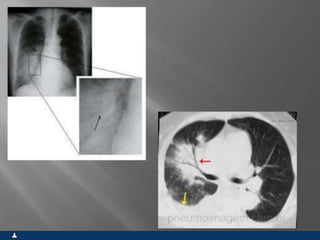

CAVIDADES

SINTOMAS SINAIS

 OLIGOSSINTOMÁTICOS

OU ESPECÍFICOS

 INSPEÇÃO NORMAL

 EXPANSIBILIDADE NORMAL

OU COM REDUÇÃO FOCAL

 FTV COM REDUÇÃO FOCAL

 HIPERSONORIDADE FOCA

 MV REDUZIDO OU AUSENTE

FOCALMENTE

 SOPRO ANFÓRICO FOCAL

 SEM ESTERTORES

BRÔNQUICOS OU

ALVEOLARES